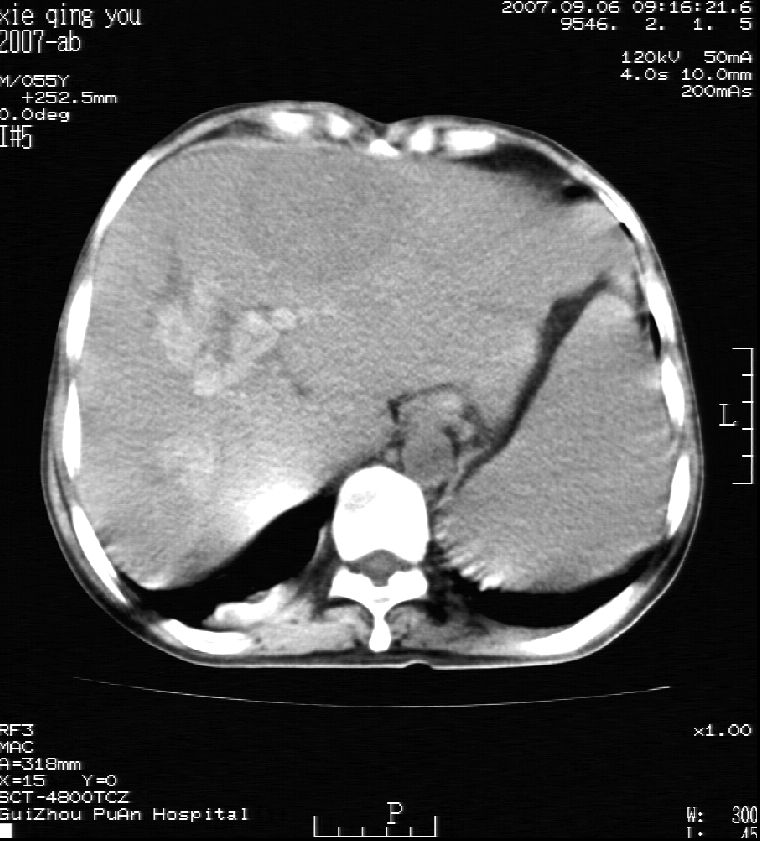

男 55岁  反复上腹痛1年,伴恶心呕吐。2005年做第一次检查后,到外院做b超检查提示肝囊肿,未做任何手术。2006年做过胆总管结石术。骨窗未见异常

2007年8月片

2007年9月片

这个病灶很有意思,怎么可能没有了呢?我考虑当时很可能是肝脏脓肿(b超示囊肿是有可能误诊的,因为影像表现都是低回声吗?),现在脓肿吸收了,肝脏萎缩,肝裂增宽了.别的肝叶代偿增大,不过现在左内叶的确有个占位,肝内多发结石,脾脏比以前大,不排除有肝硬化可能.建议增强扫描给于定性!!!!

肝硬化\\脾大,肝左叶肝癌可能性大,建议增强扫描.肝内胆管多发性结石.

1, 肝硬化,脾大;2,肝左叶肝癌可能性大,建议增强扫描.3,肝内胆管多发性结石.

考虑肝内胆管多发结石引起的肝内局部炎症,这样可以解释2005年肝右叶病灶的吸收和左叶新病灶.

肝硬化、脾大、肝内胆管多发结石。肝左叶低密度占位。建议增强扫描.排除肝癌